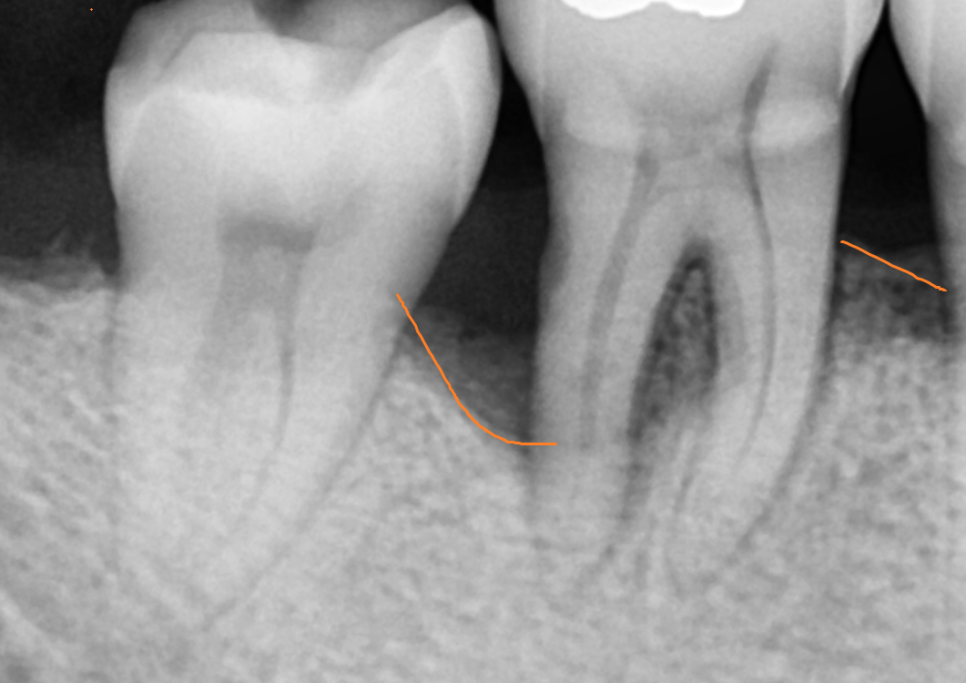

이미 이를 하나 뽑힌채로 오셨는데

치아가 없는 부위 옆에 치아도 좋지 않네요..

잇몸 내려감이 관찰

뽑은 부위는 동굴처럼 잇몸뼈가 푹 꺼졌습니다.